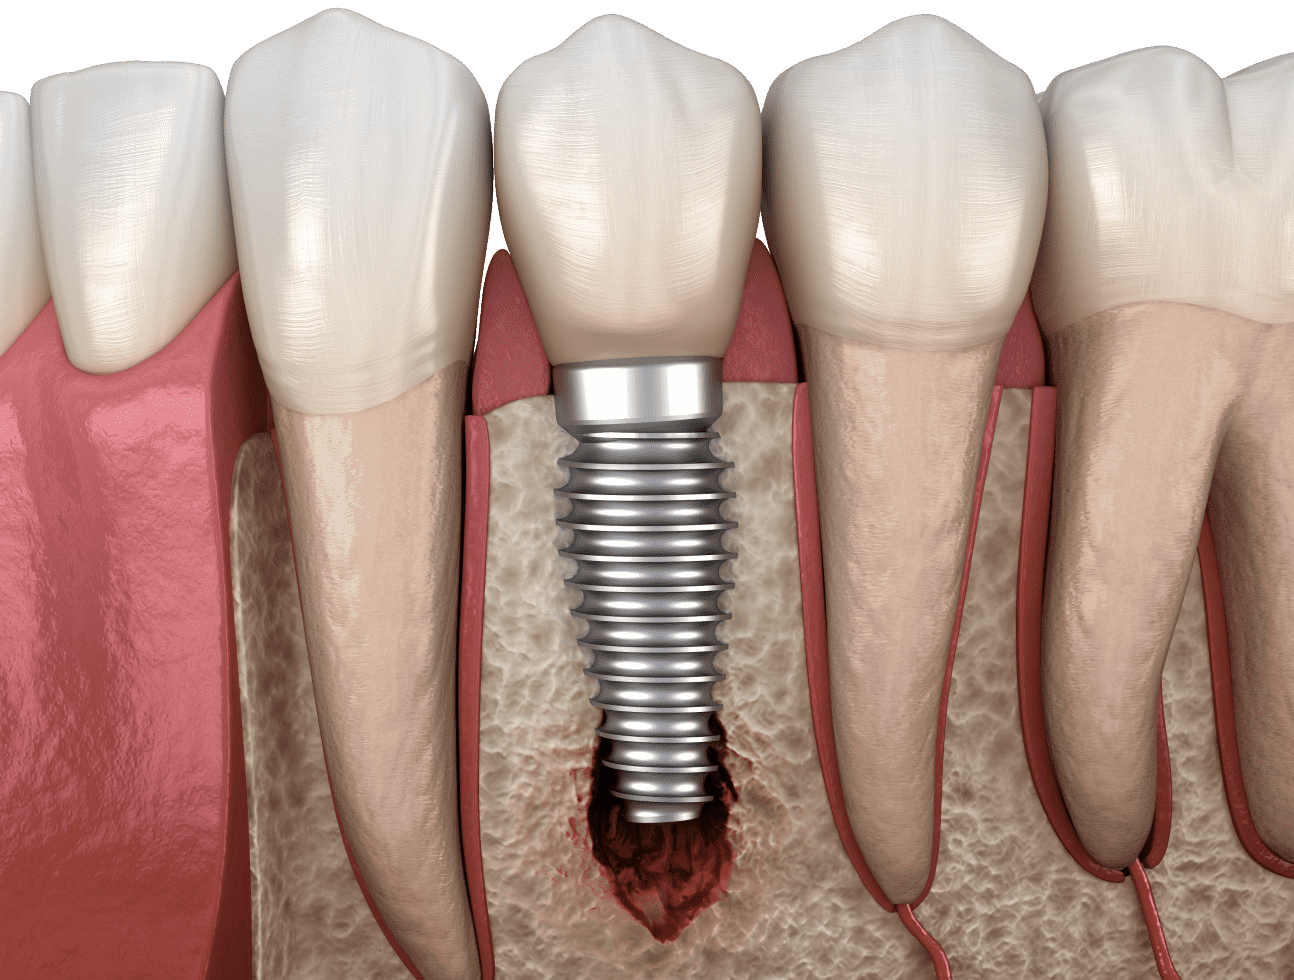

Відторгнення імпланту, симптоми та ознаки

Як і будь-яке хірургічне втручання, зубна імплантація також має ризики розвитку ускладнень. Одним із них є неприйняття організмом штучного кореня.

До відторгнення зубного імплантату можуть призвести як вік людини, так і недотримання рекомендацій лікаря.

До основних симптомів даного процесу належать:

рясна кровотеча з операційної області;

набряк обличчя та припухлість ясен;

гострий біль у районі імплантованого штифта;

штучний зуб почав хитатися;

поява неприємного запаху з рота;

підвищення температури;

запалення ясен.

Також важливо не переплутати ускладнення імплантації із нормальною реакцією організму після операції.